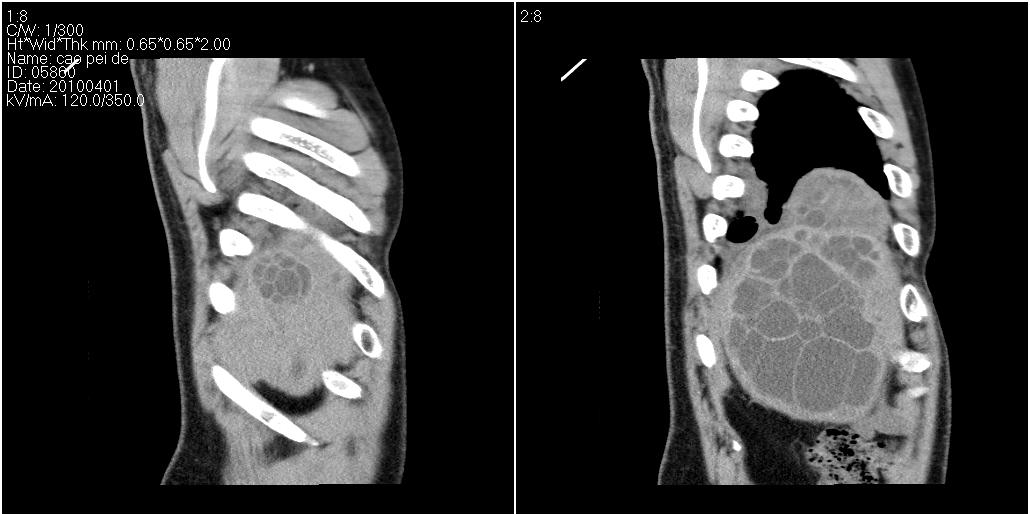

该患者70岁男性,手术后10年,现复查。2008年6月份本人曾经发过一极其类似的病例,只是部位略有差异。

多囊肝

肝脏多房性包虫囊肿

水上浮莲征,肝包虫囊肿。

肝脏及右侧胸腔包虫病。

大囊套小囊!肝脏多房性包虫囊肿